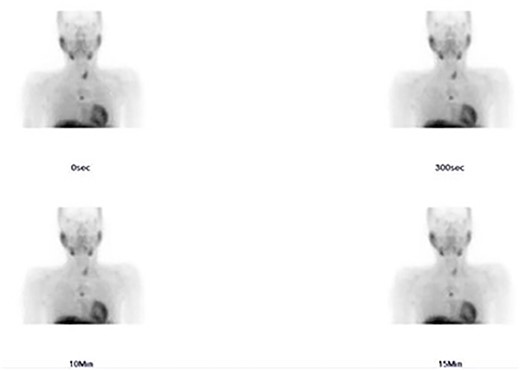

A 36-year-old male with a history of end-stage renal disease (because of polycystic kidney disease) on dialysis, for which he is on paricalcitol and sevelamer, and total parathyroidectomy with autotransplantation in the left forearm performed in 2011 for secondary hyperparathyroidism presented with generalized bone pain. Heart rate was 114 bpm, respiratory rate was 18 breaths/min, oxygen saturation was 96% and blood pressure was 136/72 mmHg. Laboratory investigations were ordered and revealed high PTH (>1300 pg per ml), low calcium (2.7 mg per dl) and low phosphate (1.8 mg per dl). A sestamibi scan was ordered and revealed hyperactive parathyroid tissue in the upper retrosternal area (Fig. 1). Removal of the ectopic parathyroid tissue was planned; however, the lesion was not localizable intraoperatively, and further chest CT with preoperative coil localization was performed, which revealed a retrosternal ectopic parathyroid tissue anterior to the ascending aorta (Fig. 2).Right thoracoscopy using fluoroscopy for ectopic parathyroid removal and lymph node biopsy was performed, and the specimens were sent to histopathology, which showed multiple nodules of parathyroid tissue with benign lymph nodes (Figs 3 and 4). A final diagnosis of parathyromatosis was made. The patient was discharged in good condition without complaints of bone pain. Upon 2-week follow-up, the patient was symptom-free and laboratory investigations revealed phosphate of 2.1 mg per dl, calcium of 2.4 mg per dl and an elevated PTH of 350 pg per ml, for which a sestamibi scan was performed and showed no evidence of uptake in the neck and mediastinum but revealed uptake in the left forearm from the previous autotransplantation.

Sestamibi scan: hyperactive parathyroid tissue in the retrosternal area.